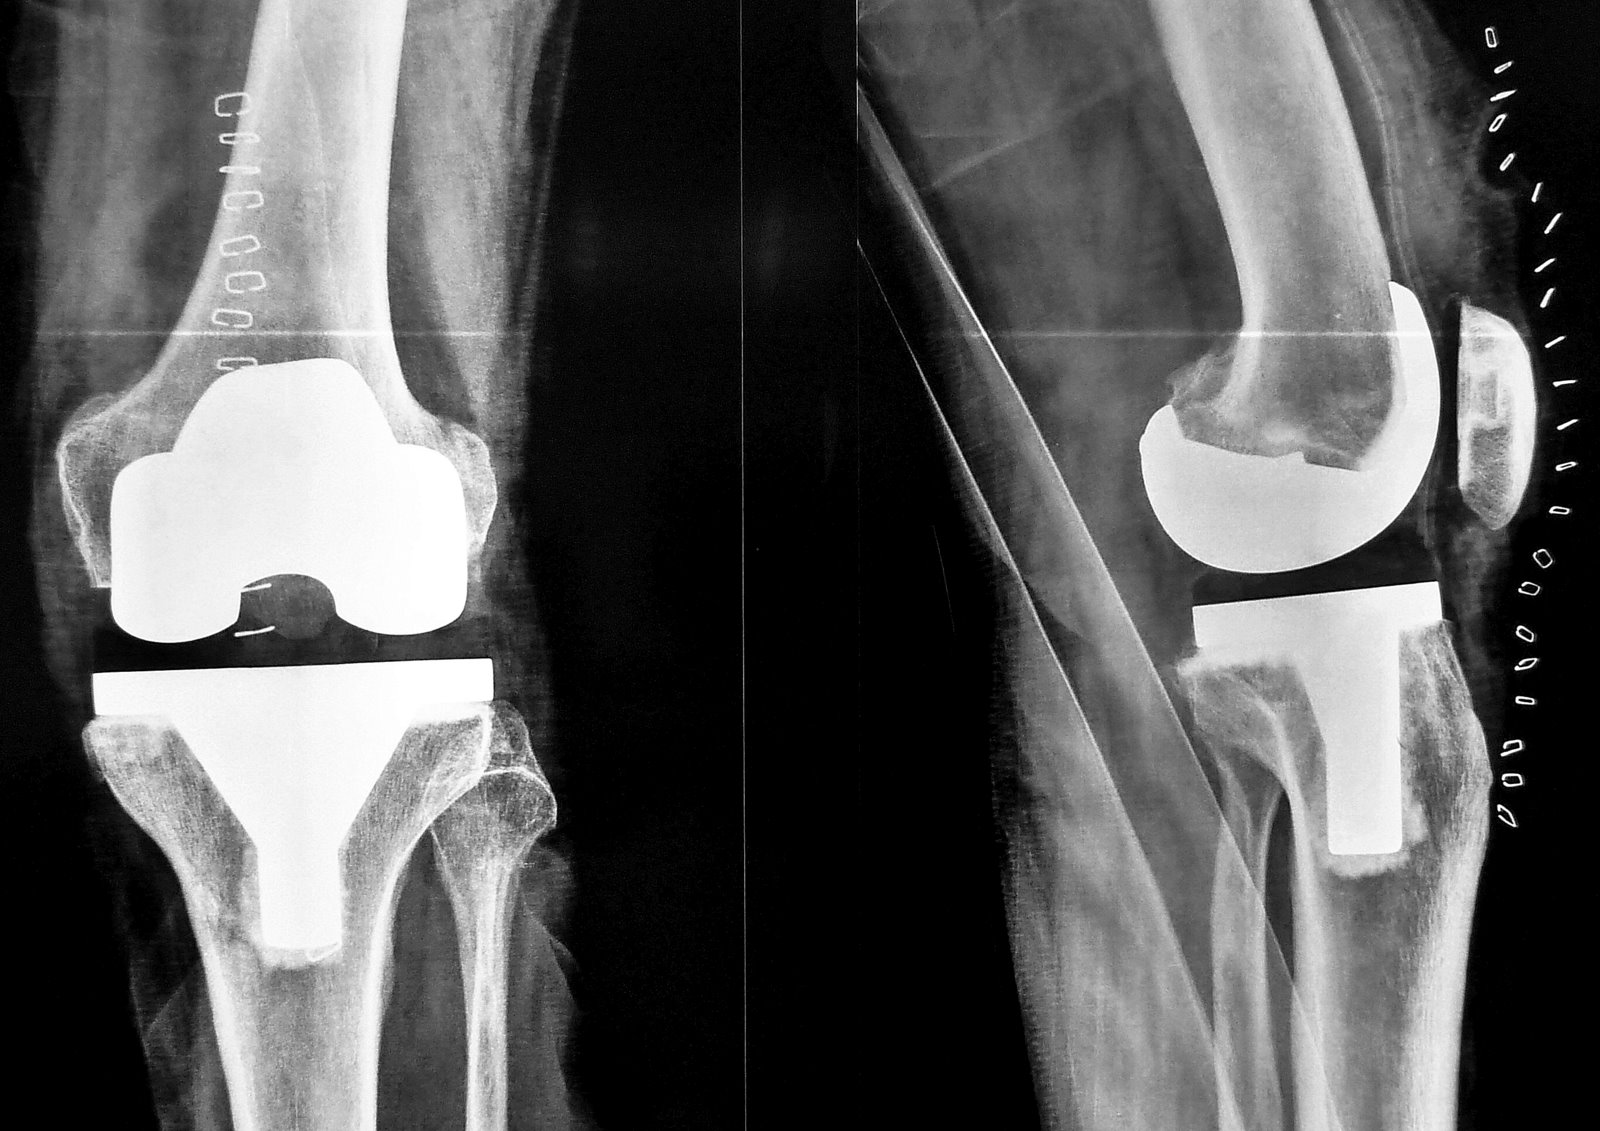

The Unhappy Total Knee Replacement Patient: Figuring out What ... Apr 07, 2019 · The condition more typically develops in those patients who achieve high degrees of flexion after a knee replacement (>120 degrees), is more common with certain knee designs like posterior stabilize (PS) > cruciate retaining (CR), when a patient has patella baja (when the patella is low riding or more distal relative to the joint line than ...

The Unhappy Total Knee Replacement Patient: Figuring out … 07.04.2019 · The condition more typically develops in those patients who achieve high degrees of flexion after a knee replacement (>120 degrees), is more common with certain knee designs like posterior stabilize (PS) > cruciate retaining (CR), when a patient has patella baja (when the patella is low riding or more distal relative to the joint line than normal), or when the femoral …